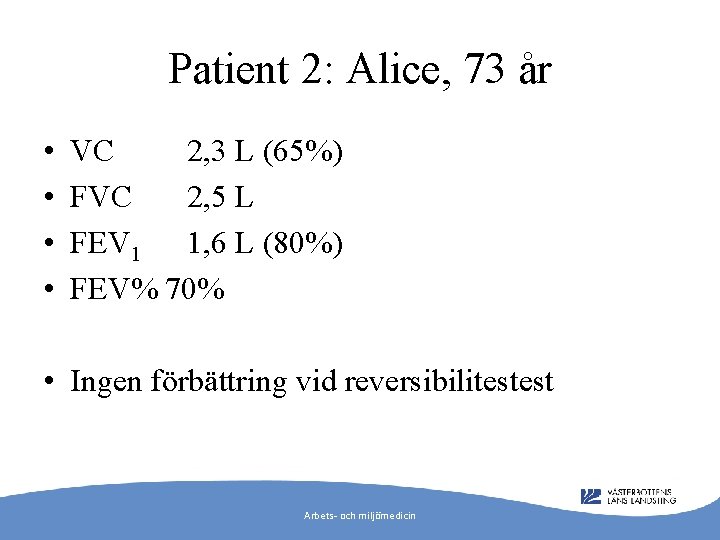

Patient 2: Alice, 73 år • • VC 2, 3 L (65%) FVC 2, 5 L FEV 1 1, 6 L (80%) FEV% 70% • Ingen förbättring vid reversibilitestest Arbets- och miljömedicin

Diagnos? • Tecken på restriktiv lungsjukdom • Remiss till klinisk fysiologi för fullständig lungfunktion och lungröntgen • Remiss till lungklinik/medicinklinik Arbets- och miljömedicin